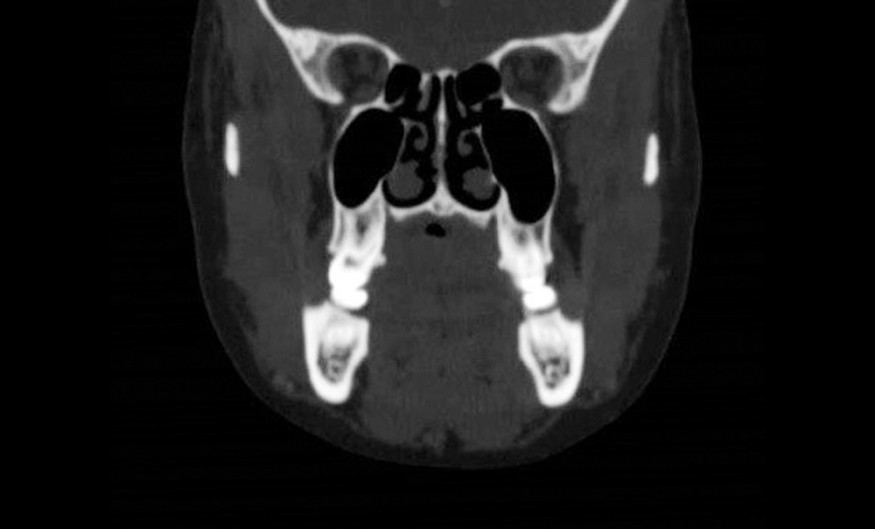

La biopsie dans ce site sans garantie d’une bonne fermeture et sans connaître la nature tissulaire de la lésion est hasardeuse. La cytoponction à aiguille fine permet d’approcher la nature bénigne ou maligne de la lésion et éventuellement le type histologique mais peut présenter des faux négatifs. C’est l’examen antomopathologique qui seul permettra de conclure. La TDM permet d’éliminer une lyse osseuse palatine en regard (fig. 2). Elle peut être complétée par une IRM.